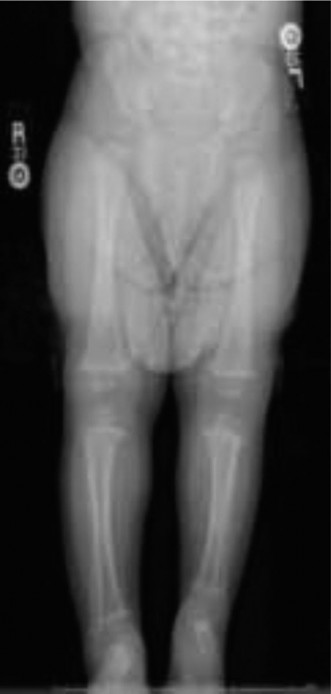

Radiographic Imaging:

- Standing Full-Length AP/Lateral Radiographs (LLDograms): Essential for accurate LLD measurement and assessment of overall mechanical alignment of the lower extremity. These are critical for quantifying angular deformities and planning osteotomies.

- Ankle and Foot AP/Lateral/Oblique Views: To delineate ankle mortise anatomy, talar morphology, and specific foot deformities, including lateral ray deficiencies and potential tarsal coalitions.